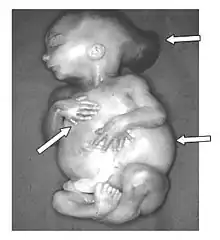

Enfin, il est le premier à distinguer un rapport unitaire dans un ensemble de malformations différentes, comme le syndrome de Meckel, dit aussi syndrome de Gruber, ou de Gruber-Meckel[5].

Les théories et interprétations de Meckel le Jeune, foncièrement vitalistes, sont devenues obsolètes[4], avec la mise en évidence à la fin du XIXe siècle, des mécanismes physico-chimiques du développement de l'embryon[8]. Toutefois, l'exactitude de ses descriptions est remarquable, par exemple la réalité et l'authentification du syndrome de Meckel a été établie en 1969[10].

La plupart de ses préparations tératologiques sont encore conservées en Allemagne, quelques-unes ont fait l'objet de nouvelles études génomiques en 2002[11].

- Beschreibung zweier durch sehr ähnliche Bildungsabweichungen entstellter Geschwister (syndrome de Meckel). Deutsches Archiv für Physiologie, 1822, 7: 99-172.